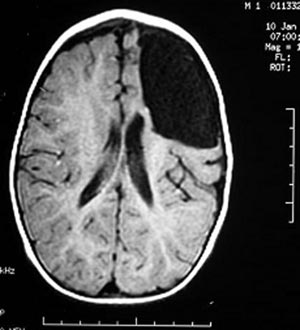

2a) Displasia cortical focal

Figura 41 e 42 - Ressonância nuclear magnética antes da cirurgia.